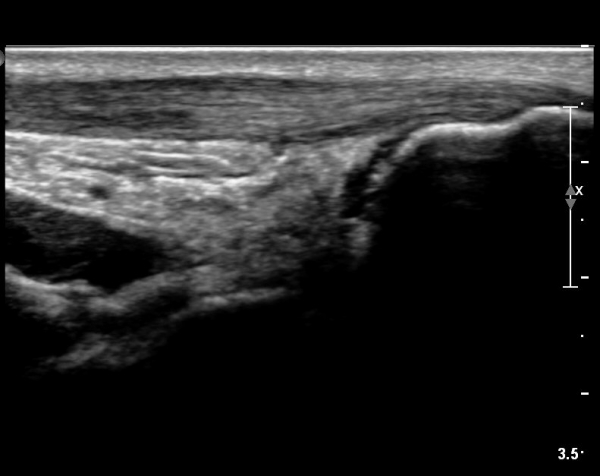

[¹ß¸ñ] simultaneosus tear of GCM and achiles tendon

pain on rt. leg( du: 1 day)

abrupt leg pain developed during foot volleyball

he walk with severe limping with no weight bearing on rt. leg. on examination, there is local tendernes at GCM and achiles tendon, severe pain with ankle dorsiflexion.

ÃÊÀ½ÆÄ °Ë»ç